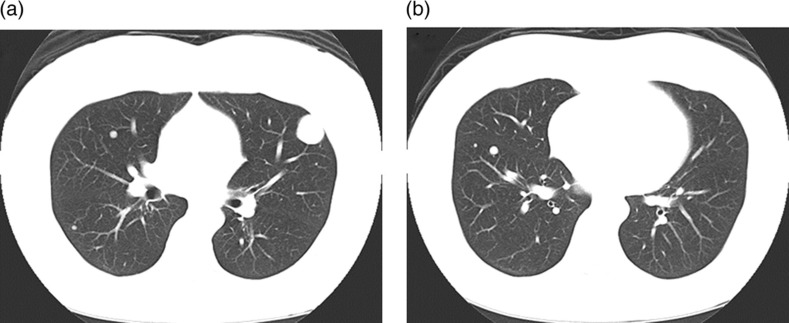

We report a case of multiple benign metastasizing leiomyoma (BML) lung nodules showing faint or non-avid uptake of F-18 fluorodeoxyglucose (FDG) (respective 1-hour early and 2-hour delayed maximum standardized uptake values; 1.3 or less and 1.2 or less) in a 50-year-old woman with a history of hysterectomy for uterine leiomyoma at the age of 38 years. When multiple lung nodules show faint or non-avid FDG uptake in a patient with a history of hysterectomy for uterine leiomyoma, BML should be included in the differential diagnosis.